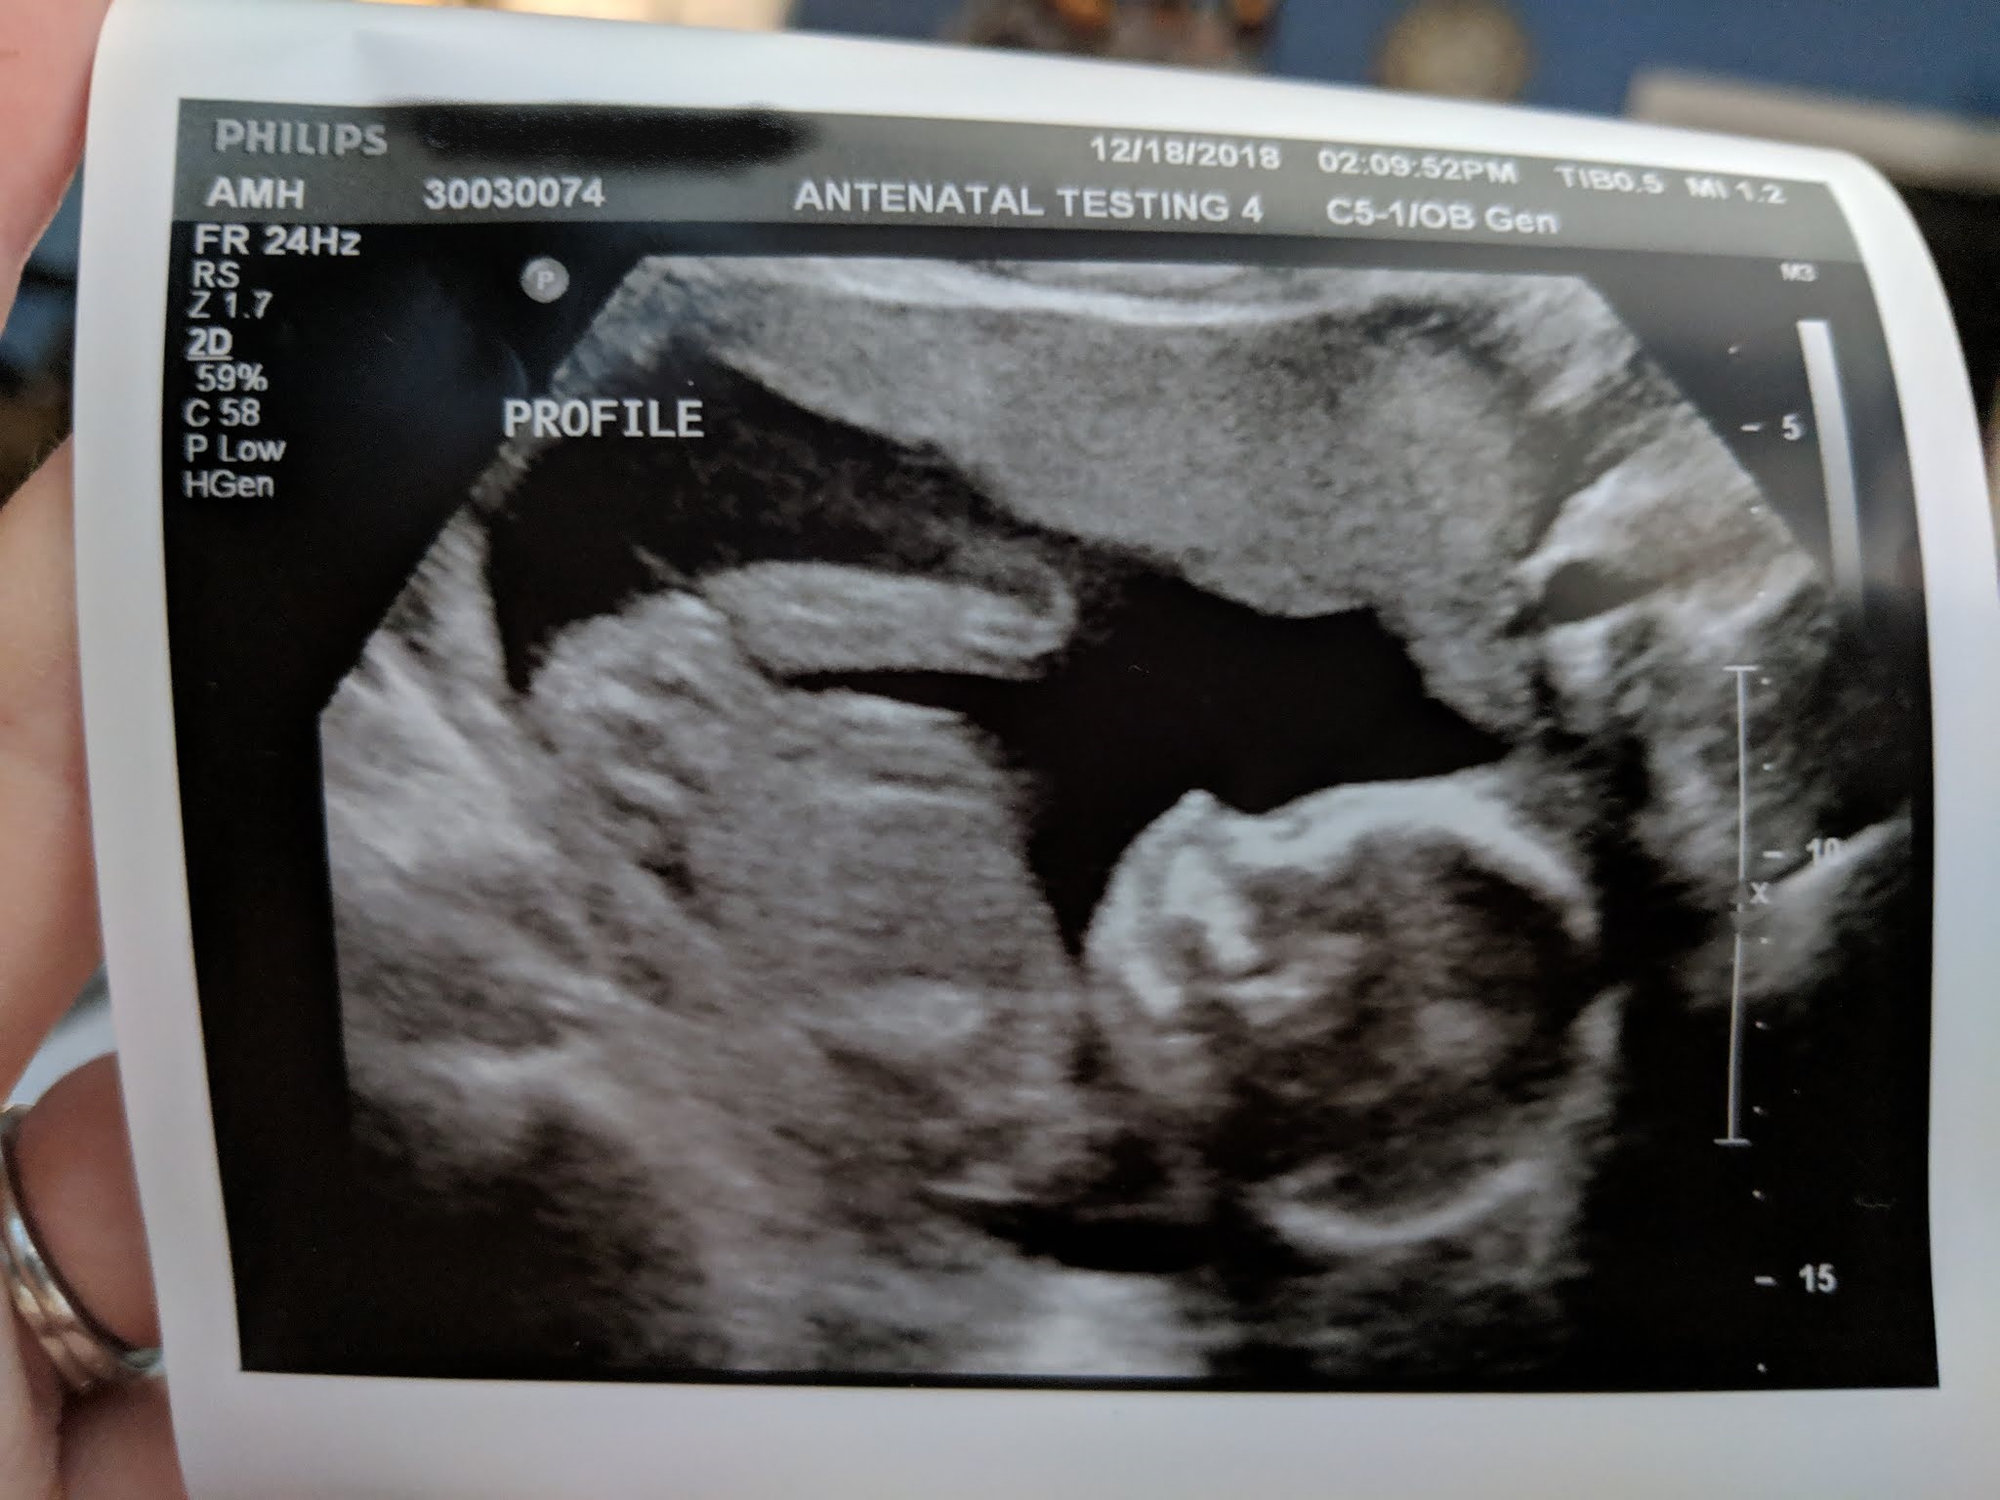

Our BABY GIRL was drinking away having lots of hiccups and big yawns! We have two hands, two feet, two arms, two legs, two kidneys, and one VERY uncooperative little girl!

@dfirstimer it was really cool! It was very strange, however, to see the movement on the screen and also feel her moving in me at the same time. Super weird, outer body experience almost!